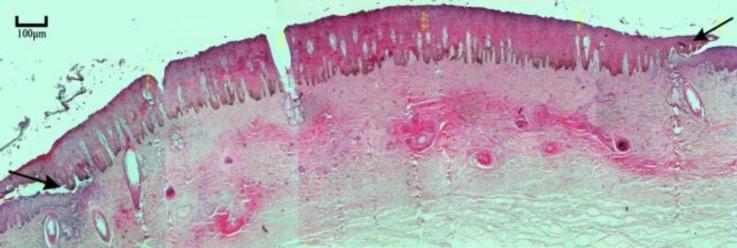

This study was conducted to evaluate the effect of subcutaneous administration of synthetic eugenol (EG) for disbudding of goat kids, as a new chemical method. Thirty apparently healthy Raieni (Cashmere) goat kids (five-day-old) were divided randomly into six groups (n = 5). In the pathology (P) groups (P, P and P according to the sample collection day after injection) an amount of 0.10 mL of EG was subcutaneously administrated in both horn buds. In the disbudding 1 and 2 (DB, DB) groups, 0.10 mL of EG, and in the control (C) group 0.10 mL normal saline was subcutaneously injected in the right horn buds, respectively. Eugenol injection in DB group was done in twelve-day-old goat kids. The left horn buds of DB, DB and C groups were considered as control of horn outgrowing. The horn buds, kidneys, liver, lung, brain and heart, tissue specimens were collected from P and P groups, and bud skin samples were collected from P group. The results showed that the EG was able to stop the horn growth in the first week of goat life. There was no significant difference between left and right horn size in the C group. Histopathological study revealed complete necrosis of bud tissue in dermal and epidermal layers, in P animals. Healing and re-epithelialization were seen in the samples taken from P group. Subcutaneous injection of the synthetic EG can be considered as a new method for goat kids disbudding.

本研究旨在评估皮下注射合成丁香酚(EG)作为一种新的化学方法用于摘除山羊羔角芽的效果。30只外观健康的拉伊尼(开士米)山羊羔(5日龄)被随机分为6组(每组n = 5)。在病理(P)组(根据注射后样本采集日分为P、P和P组),在两个角芽处皮下注射0.10 mL的EG。在去角1组和去角2组(DB1、DB2),分别在右角芽处皮下注射0.10 mL的EG,而在对照组(C组),在右角芽处皮下注射0.10 mL生理盐水。DB组在12日龄的山羊羔中进行丁香酚注射。DB1组、DB2组和C组的左角芽被视为角生长的对照。从P组和P组采集角芽、肾脏、肝脏、肺、脑和心脏的组织标本,从P组采集芽皮肤样本。结果表明,EG能够在山羊生命的第一周阻止角的生长。C组左右角大小之间无显著差异。组织病理学研究显示,P组动物的芽组织在真皮和表皮层出现完全坏死。从P组采集的样本可见愈合和重新上皮化。皮下注射合成EG可被视为一种摘除山羊羔角芽的新方法。